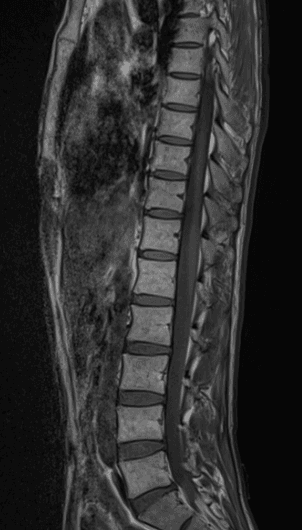

이런 경우에 골절이 아닌지 오해하시는 경우가 많은데 골절이 아닙니다.

골절의 경우에는 T1 영상에서 조영이 떨어지고 fat suppression T2 영상에서 조영이 증가하는 소견을 확인해야합니다.

골절이 아니면 왜 저렇게 보이는지 까지는 제가 잘 모르지만 저 소견을 이상소견으로 보이는 않습니다.